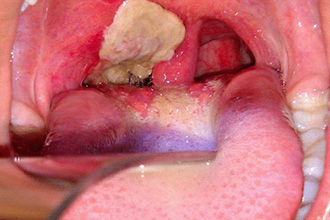

Абсцесс миндалины

Опасность ангин заключается не только в возможных отдаленных осложнениях, но и в возникновении местных гнойных процессов. Наиболее распространенным из них является абсцесс миндалины. При этом, помимо усиливающейся боли при глотании, возникает острая боль в горле. Состояние пациента постепенно ухудшается, он испытывает трудности с открытием рта, а температура тела повышается.

Причинами такого осложнения часто становятся неправильное и несвоевременное лечение гнойных ангин. Консультация отоларинголога помогает уточнить диагноз и назначить необходимые медикаменты. При осмотре ротовой полости заметна увеличенная миндалина, что приводит к смещению языка в сторону. Пациенты в таких случаях жалуются на сильную боль в горле. В большинстве ситуаций данное состояние требует срочного хирургического вмешательства.